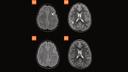

Case 3

10-year-old male, 2 week history of morning headaches, waking up at night. History of anxiety. Suspected radiological isolated demyelinating type lesions. Top row GOBrain (5A, B: axial T2 TSE, and axial T2 TSE FLAIR). Bottom row, conventional sequences (5C, D: axial T2w, and axial FLAIR). The images exemplify the same number and size of white matter lesions (arrows) in the GOBrain-5-minute protocol (top row), compared to the conventional protocol (bottom row).